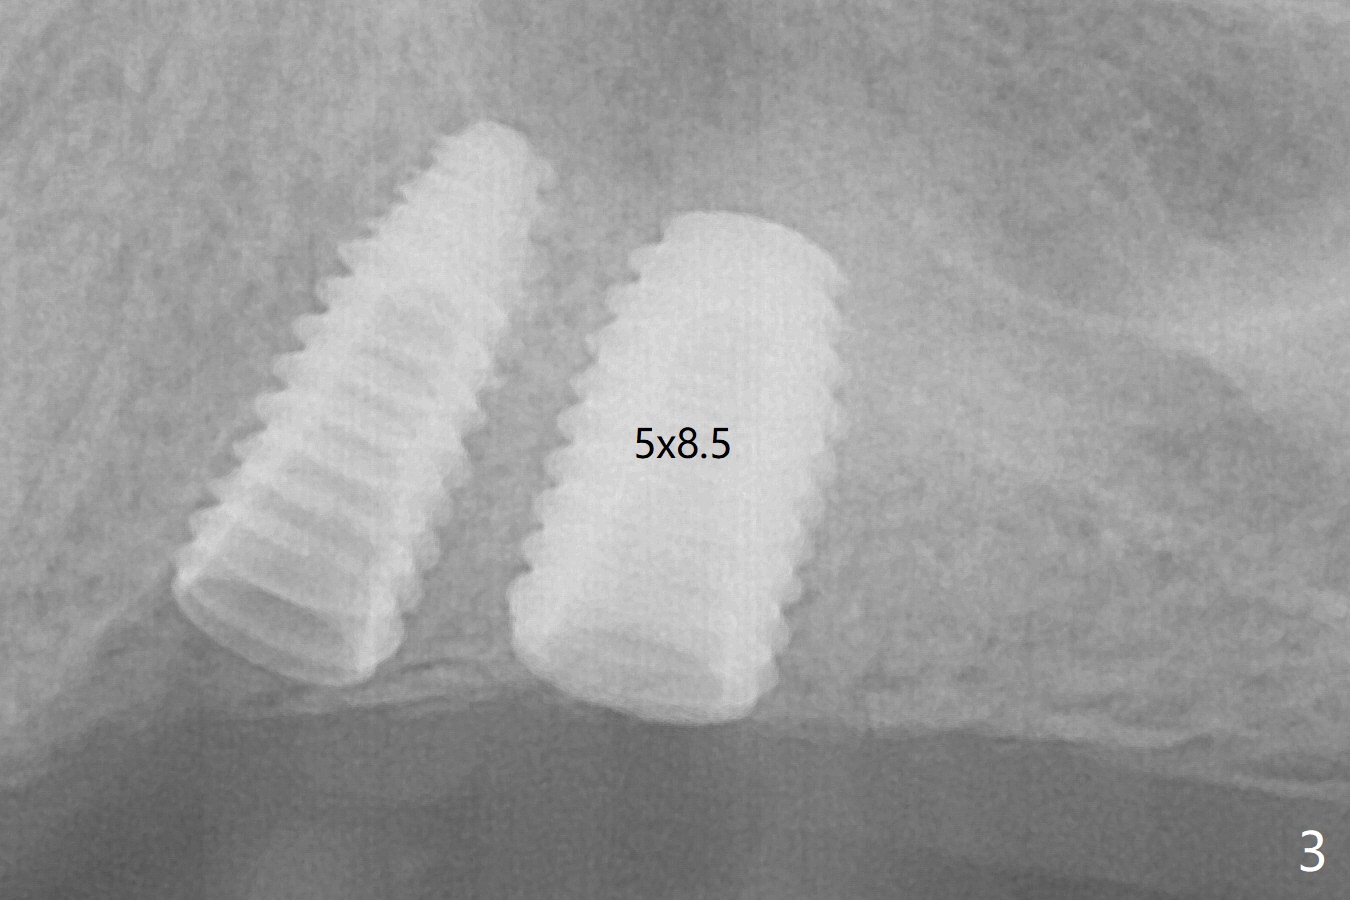

Three months post #14 implant removal and bone graft, the existing guide is reused, but no stop fixture mount cannot be inserted into #13 implant as an anchor. After 3.5x7.3 mm drill with 12 mm offset, the bottom of the osteotomy is not so hard; therefore sinus lift is conducted with allograft and 4x10 mm dummy implant (Fig.1). The lifted sinus floor is in fact not noted during the surgery (Fig.1 dashed red line). Sinus lift continues with bone graft and 4.5x10 mm (Fig.2); bone graft is squeezed out (*). The final implant (5x8.5 mm) is not seated until use of 4.5x7.3 and 4.0x10 mm drills (Fig.3). The implant is further placed free hand until subcrestal distal; since the torque is not high, a healing screw (S) is placed with packing allograft around the plateau of the implant (*). By placing a 4.5x4.5(4) mm cemented abutment at #13, a provisional is fabricated with extension to cover the bone graft at #14. When the provisional dislodges 1.5 months postop, #14 wound does not heal with the erythematous gingiva and exposed healing screw (Fig.5). Diabetes is not well controlled (HbA1c >6% (normal 4-5.6%)). Poor oral hygiene is another contributing factor in failure. After cleaning and torque 30 Ncm of the abutment at #13, impression is taken. In fact the tooth #12 has lost the palatal cusp (Fig.6 <); a crown will be fabricated at #12 when the implant at #14 osteointegrates. The implant at #14 is uncovered 5 months postop (Fig.7 (6.8x3 mm healing abutment)). The implants of #13 and 14 are close to each other, which is related to the slanted ridge at #13 (^). The osteotomy and the implant slide distal during placement (arrow). The implant in the slanted ridge should be intentionally placed mesial to compensate for the shifting. Or the ridge should be trimmed precisely; open surgery is necessary. A 5.2x5.5(4) mm cemented abutment is apparently completely seated with 35 Ncm torque 6 months postop (Fig.8). Although the distal plateau of the implant is exposed when the provisional is removed, post cementation bitewing shows equicrestal placement distal (Fig.9).